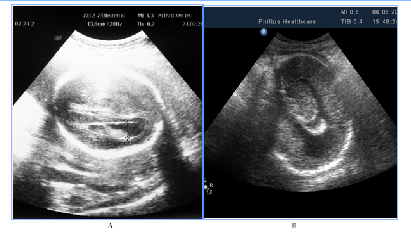

In 5fetuses with severe prolonged course of placental dysfunction we antenatally detected modified insular complex with anomalously broad lateral (Sylvian) sulcus as a signs of abnormal gyration and sulcation (Figure 7). US images of cortical dysplasia in our study were associated with fetal intrauterine growth retardation (IGR), Oligohydramnios, metabolic acidosis and neuro infection. These fetuses had adverse GPO (3cases) and extremely unfavorable CPO (2cases) (Figure 8).

Figure 7NSG of two fetuses of the same gestational age (29 GW) with normal brain image (A), also with a signs of cortical dysplasia (B).

NSG of two fetuses of the same gestational age (29 GW) with normal brain image (A), also with a signs of cortical dysplasia (B).